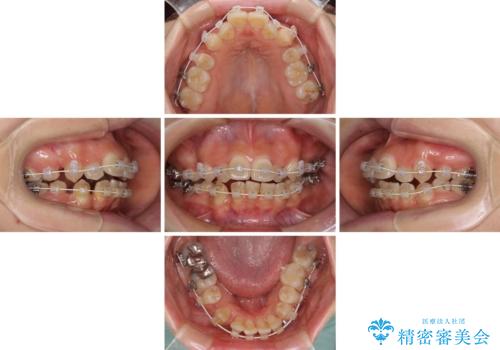

- 矯正装置

- 審美装置

- 治療期間

- 2年

- 治療回数

- 10-30回